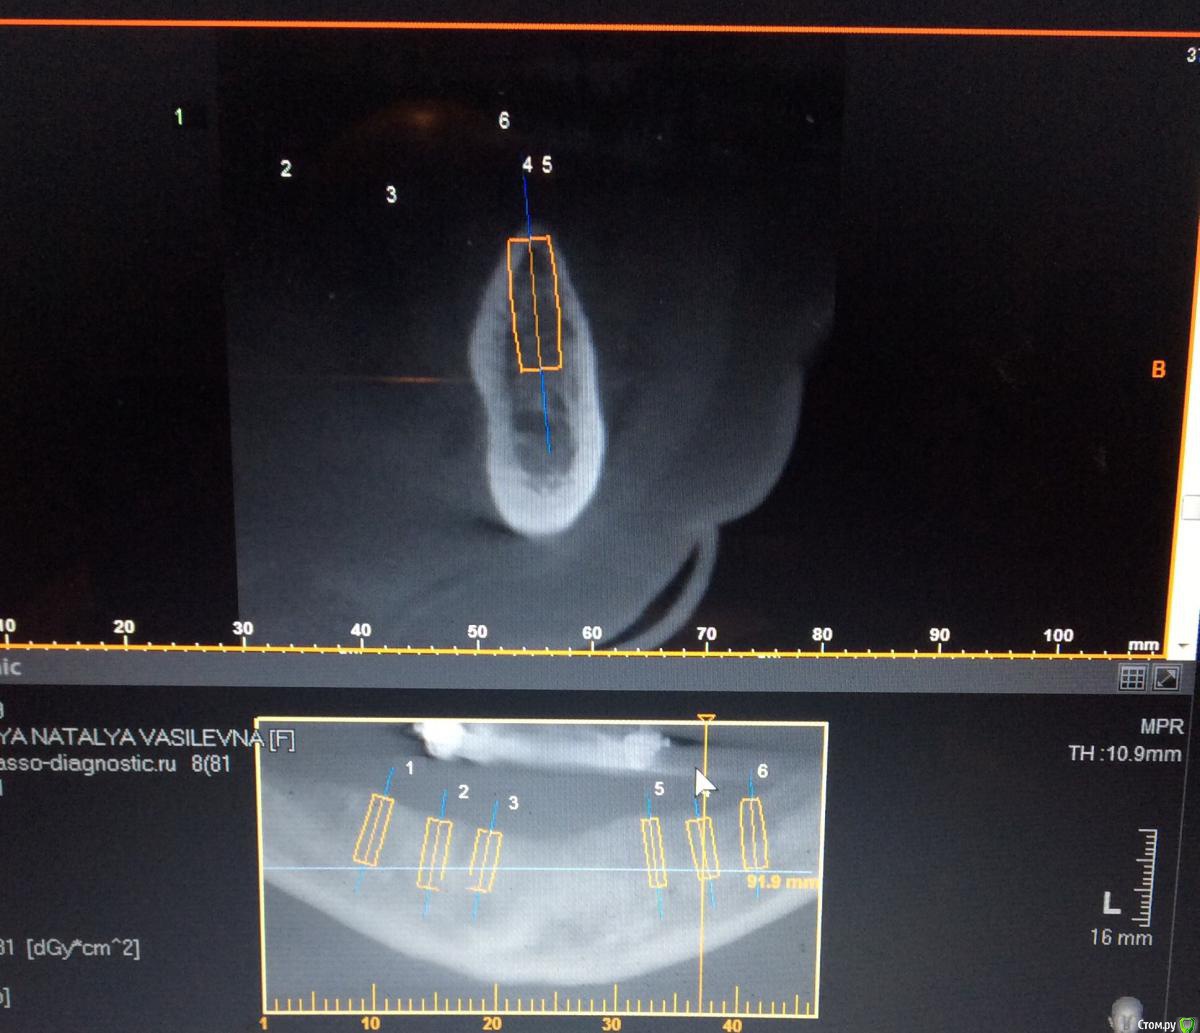

Евгений Ходыкин Опубликовано 27 мая, 2015 Поделиться Опубликовано 27 мая, 2015 Сделайте срезы планнинга по каждому имплантату. Там будет понятно. Ссылка на комментарий

Neilrus Опубликовано 29 мая, 2015 Автор Поделиться Опубликовано 29 мая, 2015 Сделайте срезы планнинга по каждому имплантату. Там будет понятно.46з45з44з 34з35з36з Может можно воссатновить на двух микроимпл только от клыка до клыка чтобы губа не западала и для сохранения высоты? Ссылка на комментарий